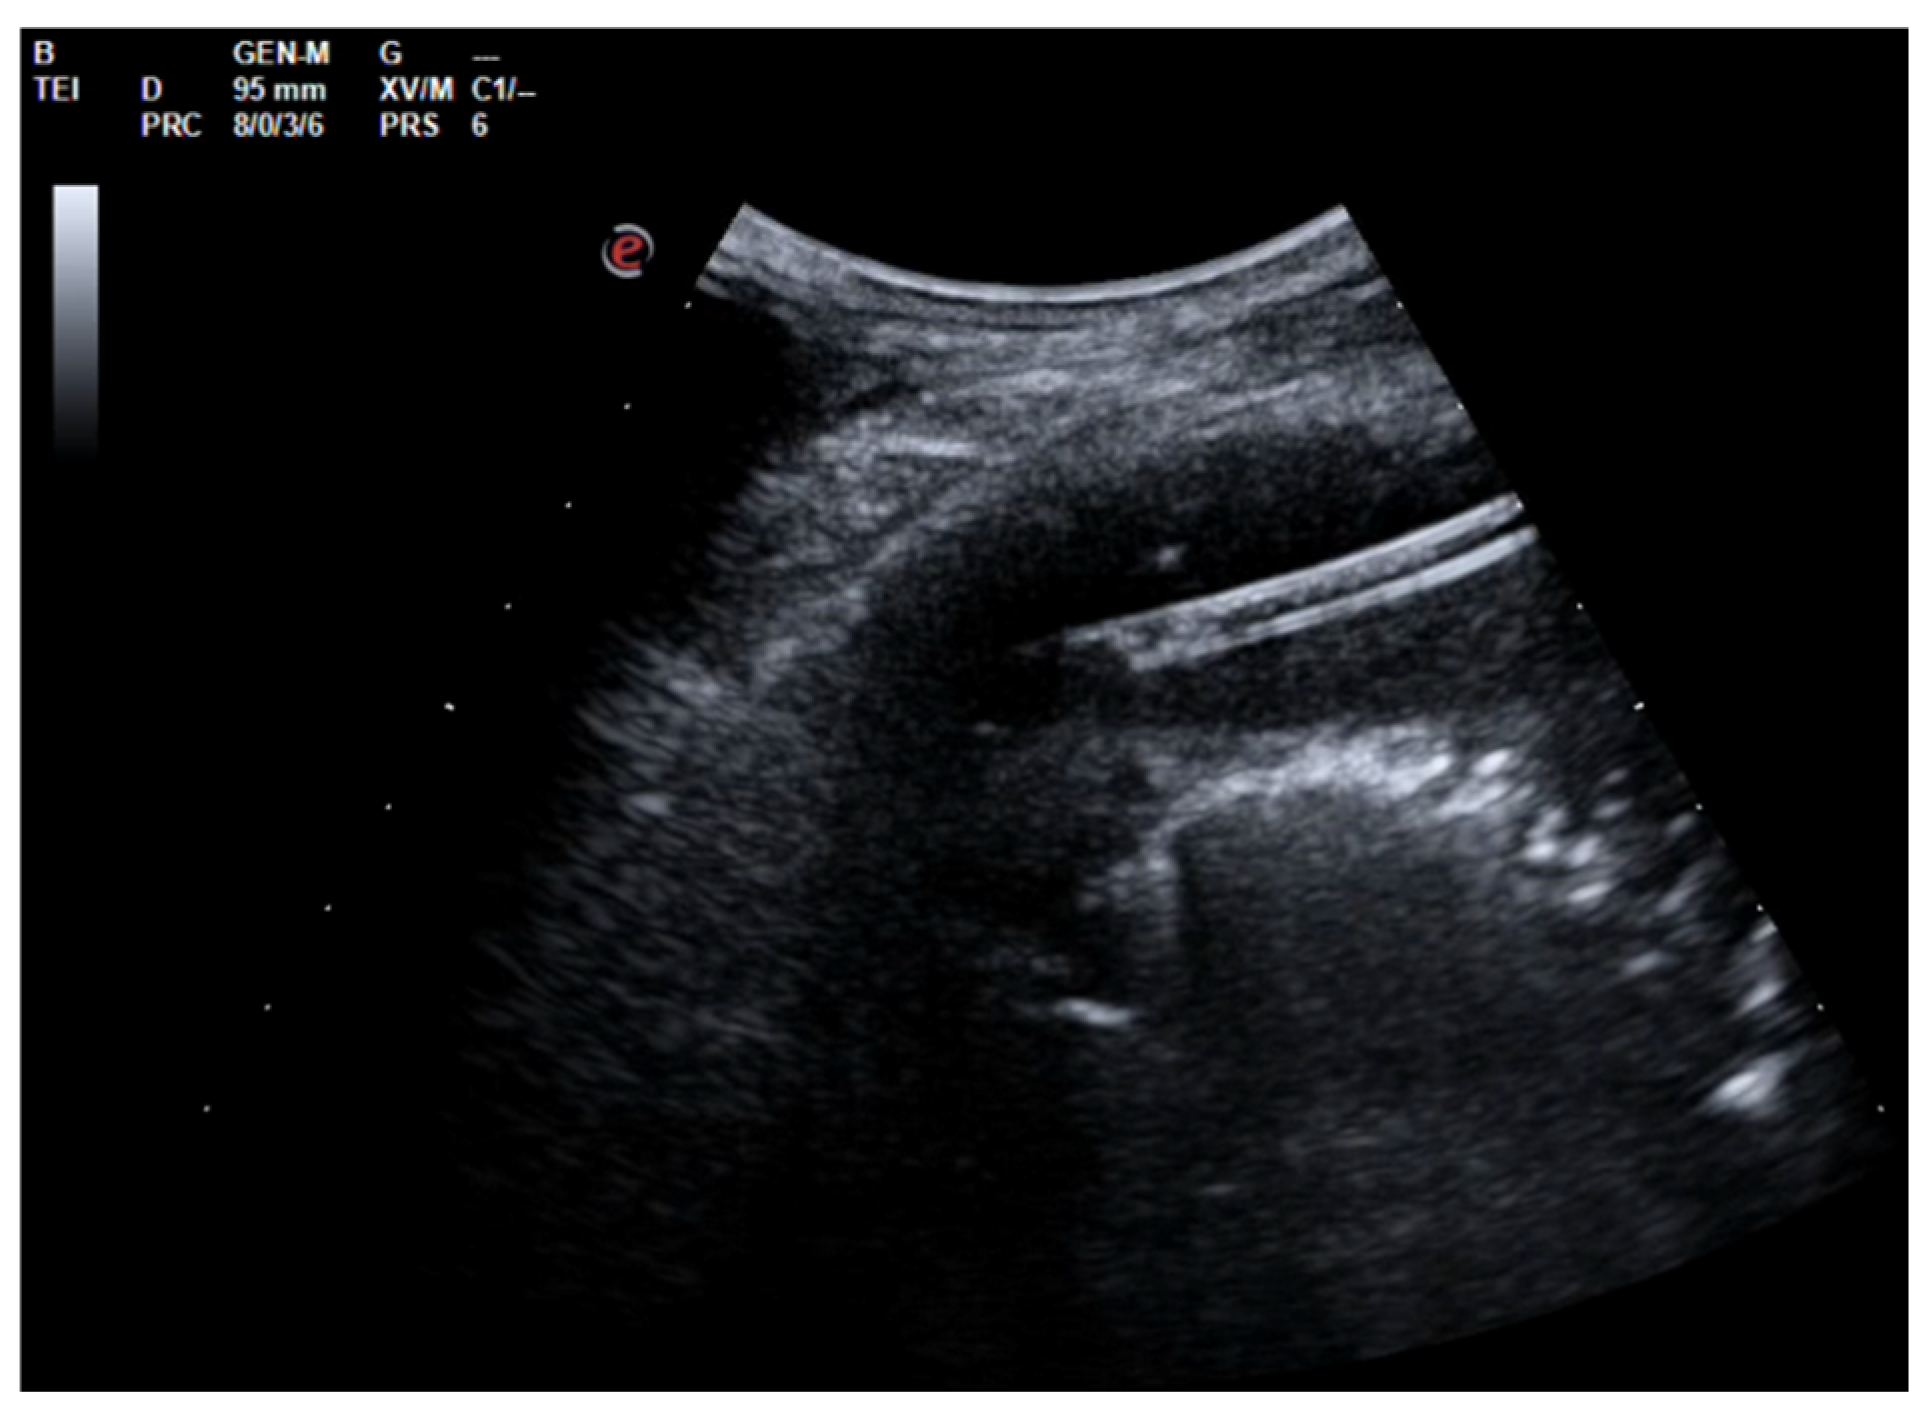

After the placement of a chest tube, pleural fluid samples were sent for microbiological and physicochemical analysis, which confirmed the diagnosis of pleural empyema. Two days after the placement of the chest tube, the fluid flow decreased. To break up the fibrin pockets present in the empyema and promote the complete evacuation of the fluid, irrigation of the pleural cavity with 200,000 UI of urokinase in 50 mL of saline solution was performed under US guidance (Figure 2).

Figure 2. Chest US during pleural lavage with urokinase. Star: distal end of chest drain; Arrow: spread of fluid.